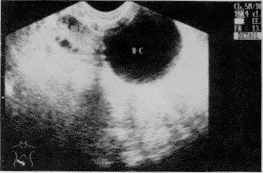

结果:24例患者中,发生在右侧11例,左侧13例,囊肿最小直径3.8cm,最大12.5cm,均为单房,圆形囊壁薄而光整,内为无回声暗区(图1)。其中1例内壁有乳头状凸起,米粒大小数个。超声误诊1例,术后诊断为子宫体前壁囊肿,诊断符合率96%。

图1 R-C:右卵巢冠囊肿 RO:右卵巢